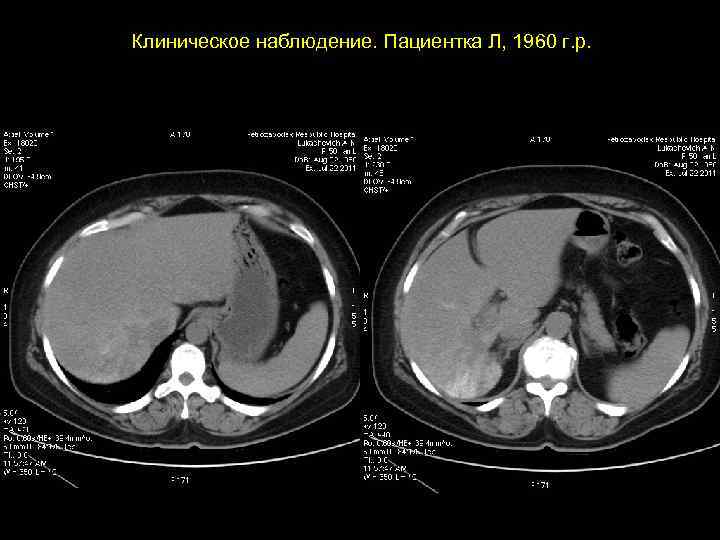

АКТУАЛЬНЫЕ ВОПРОСЫ РЕНТГЕНОЛОГИИ ЛУЧЕВАЯ ДИАГНОСТИКА ОЧАГОВЫХ ПОРАЖЕНИЙ ПЕЧЕНИ ЗЛОКАЧЕСТВЕННЫЕ ОПУХОЛИ ПЕЧЕНИ Гепатоцеллюлярный рак (гепатома) Компьютерно-томографическая семиотика: - дефект неправильной формы - с неровными, недостаточно четкими контурами - плотность равна или чуть ниже плотности неизмененной паренхимы - после контрастного усиления выраженная неравномерность структуры - часто присутствует инвазия в систему портальной или печеночной вены

Клиническое наблюдение. Пациентка Л, 1960 г. р.

Та же пациентка